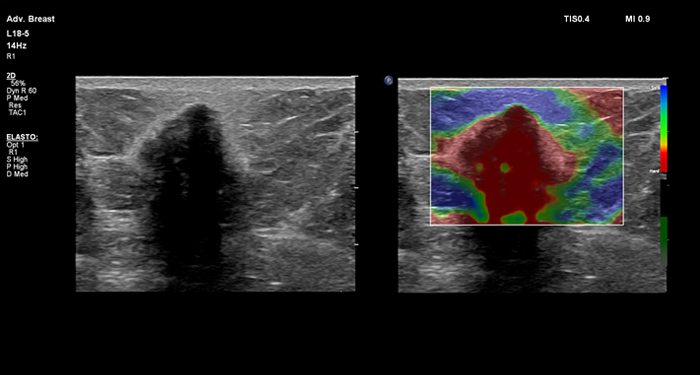

At the touch of a button, the new MaxVue high-definition display brings extraordinary visualisation of anatomy with 1,179,648 additional image pixels compared to a standard 4:3 display format mode. MaxVue enhances ultrasound viewing during interventional procedures and provides 38% more viewing area to optimise the display of dual, side/side, biplane, and scrolling imaging modes.

MaxVue offers a 38% greater viewing area.

MaxVue offers 1,179,648 additional image pixels compared to a standard 4:3 display format mode.